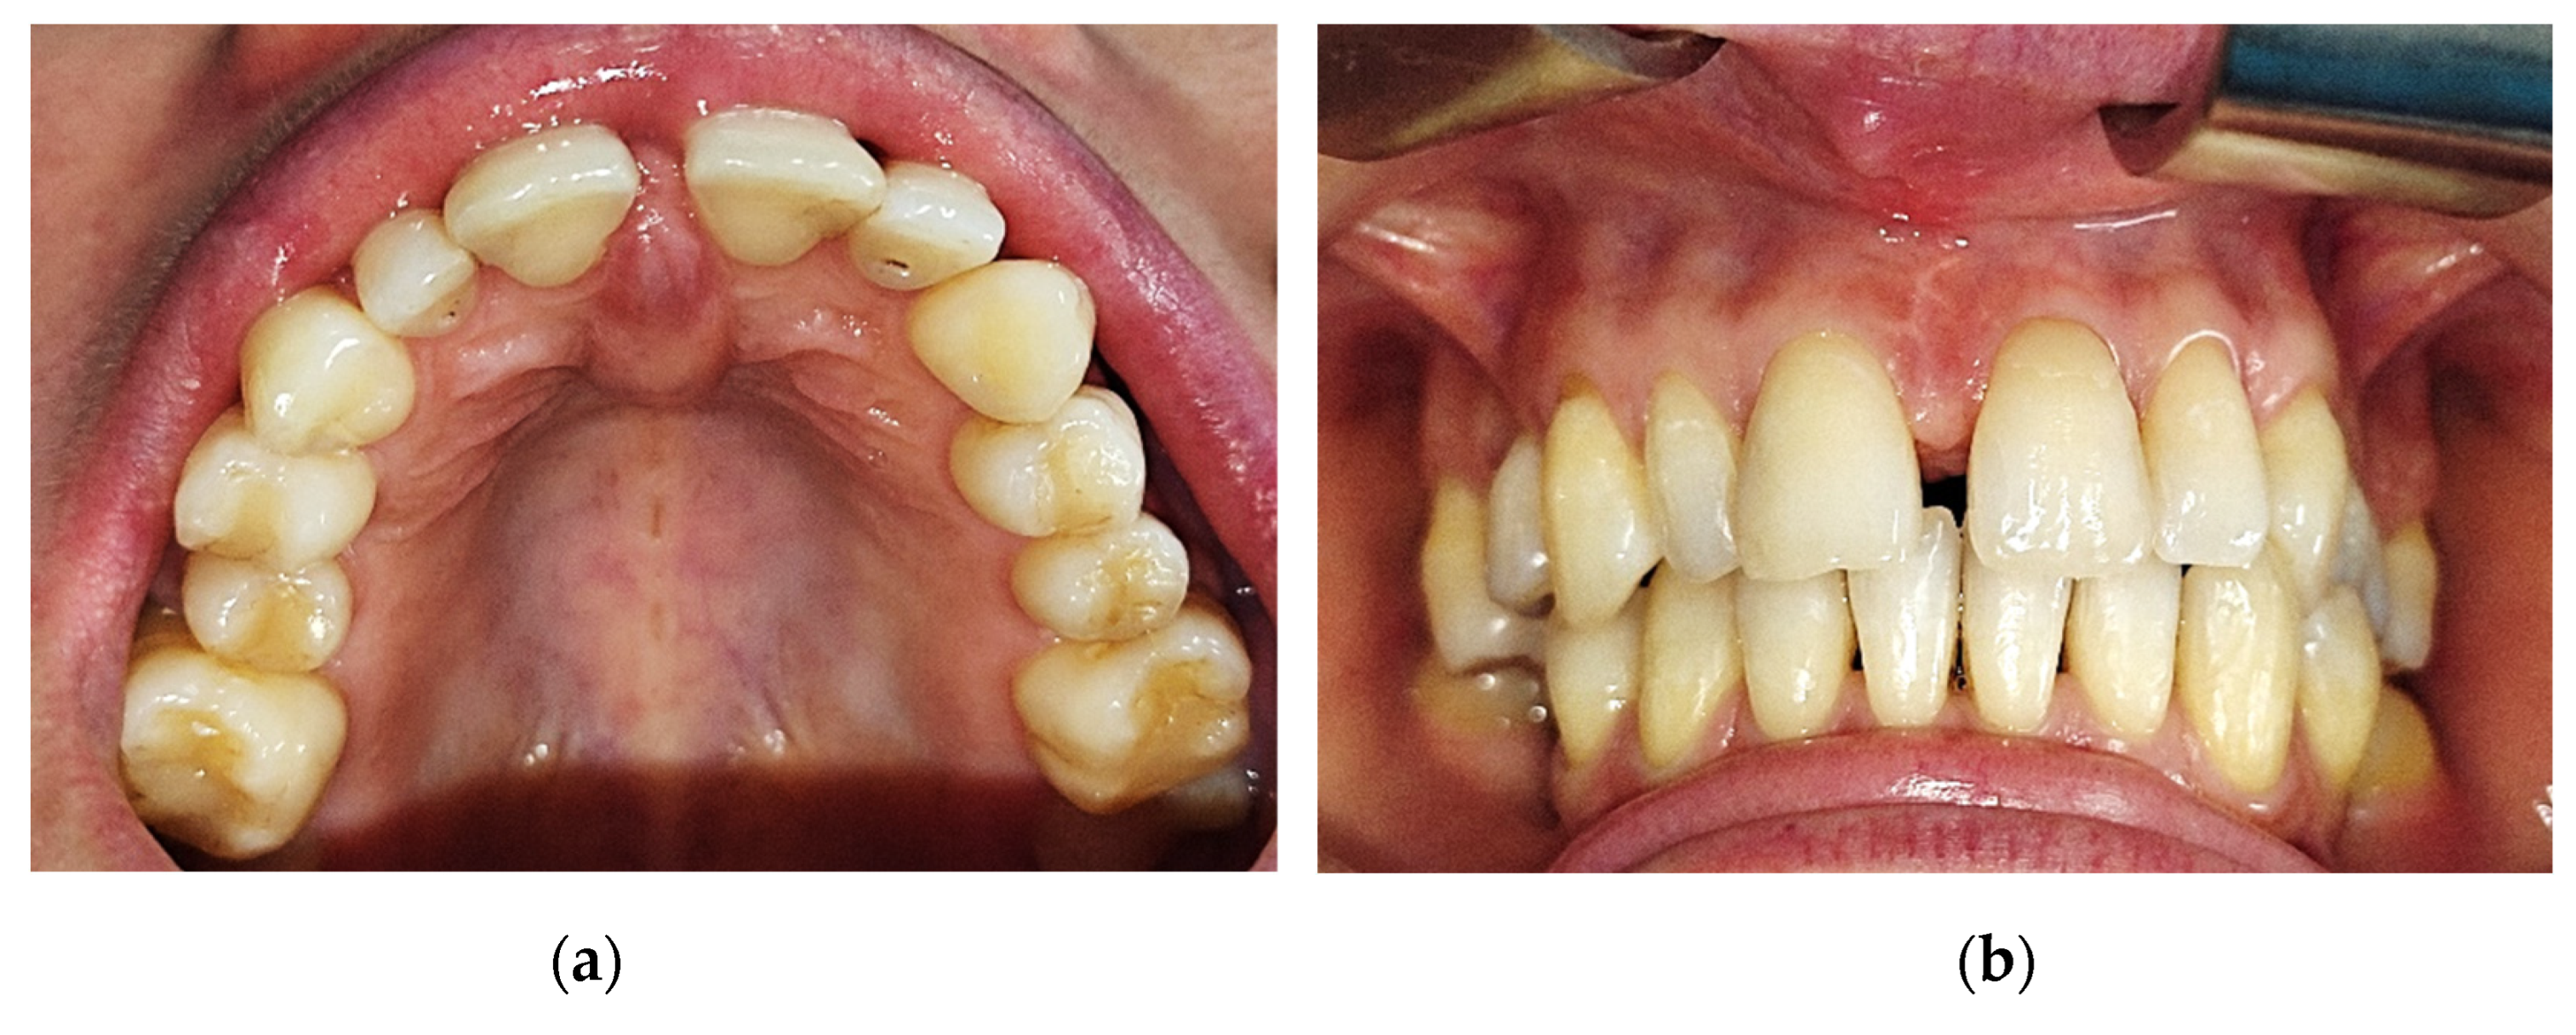

The tumor had a shape of a droplet, well delimited, with a dimension of approximately 1,5 cm (sagittal plane) / 1 cm (transverse plane), with a nodular lower pole located at the median palatal fibromucosa, extended between the bilateral palatal rugae. It had a pink tint, smooth surface, soft, resilient, depressible consistency. The upper pole of the tumoral apex was located interdentally between the superior central incisors (1.1/8-2.1/9). On the buccal side of the alveolar crest, the lesion was in contact with the crestal insertion of a hypertrophic upper labial frenulum, having a reddish color and a slightly firmer consistency, apparently fixed to the underlying bone (Figure 1).

The clinical examination also revealed a dento-alveolar incongruence with the presence of a maxillary interincisal diastema of 2mm and a slight distal tipping of the right upper central incisor, with delicate coverage, that might be associated with the presence of the mentioned tumor. Furthermore, a median buccal gingivo-mucosal scar is present between the two upper central incisors 1.1/8 -2.1/9, the patient affirming a previous surgical intervention for a frenoplasty of the upper labial frenulum.

The cone beam computed tomography image (CBCT) does not reveal any changes of the subjacent bone structure in the anterior hard palate, suggesting the sole involvement of the soft tissue (Figure 2).

Figure 1. Intraorally aspect: (a) Aspect of the tumoral lesion at the level of the incisive papilla and anterior palatal fibomucosa; (b) Aspect of the tumoral lesion (buccal view), interincisal diastema and the gingivo-mucosal scar.